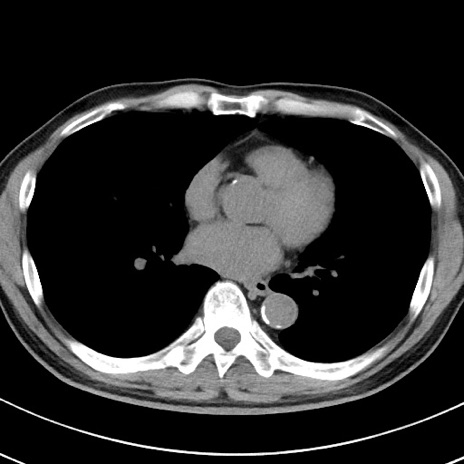

【腹部TIPS】症例29 参考症例 CT(横断像)

症例

70歳代男性